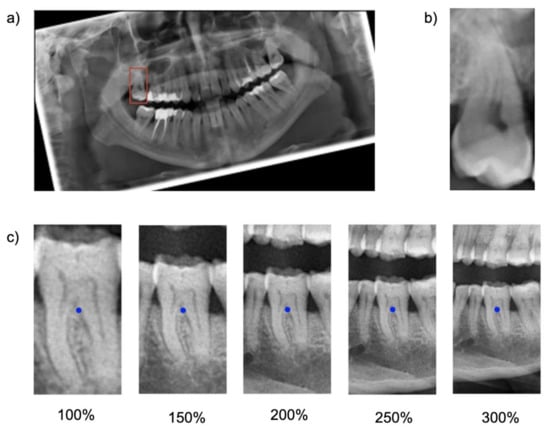

Cropping was repeated five times, each time with varying regional context information: The baseline bounding box size (100%) was scaled up to capture 150%, 200%, 250% and 300% of the baseline bounding box. The original aspect ratio was kept constant (see Figure 1). Note that the tooth considered for the classification task was consistently located within the center of each image segment.

Figure 1. Visualization of data preparation steps. (a) Panoramic radiograph with an annotated bounding box around one tooth. The image is rotated as required by the cropping algorithm, which extracts the image segment captured by the bounding box. (b) Baseline size (100%) of the image segment covering the area captured of the bounding box. (c) Visualization of increasing image segment sizes from left to right. 100% captured image segments with the size of the annotation bounding box. 300% covered image segments with the size of the bounding box upscaled by a factor of 3.